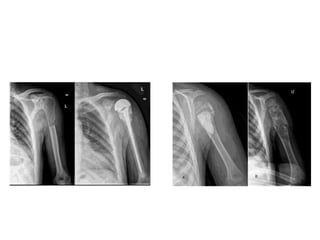

Fracturas de porción superior del húmero:

Son necesarias dos radiografías: anteroposterior y axial. También

es conveniente realizar la proyección lateral de hombro.

Exámenes paraclínicos. Fractura declavícula: Rx. Simple de hombro en proyección antero-posterior que incluya la articulación esterno-clavicular hasta la porción lateral del húmero. Agregar radiografía de tórax si se sospecha neumo o hemotórax. TAC cuando se sospecha de lesión intra-articular o cuando la fractura se encuentra en los extremos del hueso. TAC + reconstrucción 3D para evaluar consolidación de la fractura o cuando hay fractura desplazada. GPC. Tratamiento de fractura de clavícula en el adulto. Catalog Mtro Guías Pract Clin IMSS-584-12. http://www.cenetec.salud.gob.mx/descargas/gpc/CatalogoMaestro/584_GPC_Fxclaviculaenadulto/584GRR.pdf

• 29.

Fracturas de porciónsuperior del húmero: Son necesarias dos radiografías: anteroposterior y axial. También es conveniente realizar la proyección lateral de hombro. Patología Traumática. Primera Sección. 1. Fracturas del miembro superior. Fractuas del húmero. http://escuela.med.puc.cl/publ/OrtopediaTraumatologia/Trau_Secc01/Trau_Sec01_22.html